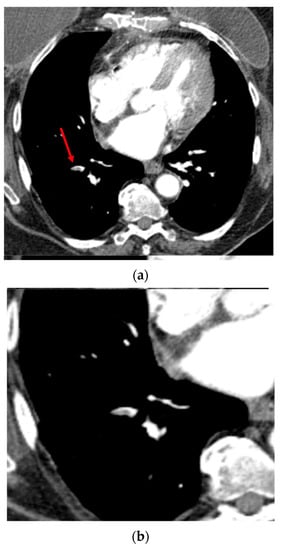

Figure 2.

Axial CTA image. Example of segmental pulmonary embolus (PE) in the right lower lobe (filling defect within the arterial lumen), correctly detected by the CINA-PE software considered as a true positive case. Top (a): The red arrow shows the clot within the arterial lumen. Bottom (b): Axial image targeted on the right lower lobe.

The AI-powered algorithm achieved its primary endpoint of lower 95% CI bounds ≥80% for sensitivity and specificity. As presented in Table 2, the sensitivity was 91.4% [95% CI: 86.4–95.0%], the specificity was 91.5% [95% CI: 86.8–95.0%], and the area under the receiver operating characteristic curve (AUC) was 0.92 [95% CI: 0.88–0.94] (p < 0.0001). The ROC curve is illustrated in Figure 1. Among the 387 tested data, 354 cases provided no difference between the operators’ visual assessments (ground truth) and the automatically computed results provided by the application (Figure 2), leading to an accuracy of 91.5% [95% CI: 88.2–94.1%] (Table 2). The MCC was 0.83, which is a factor of a very good prediction.